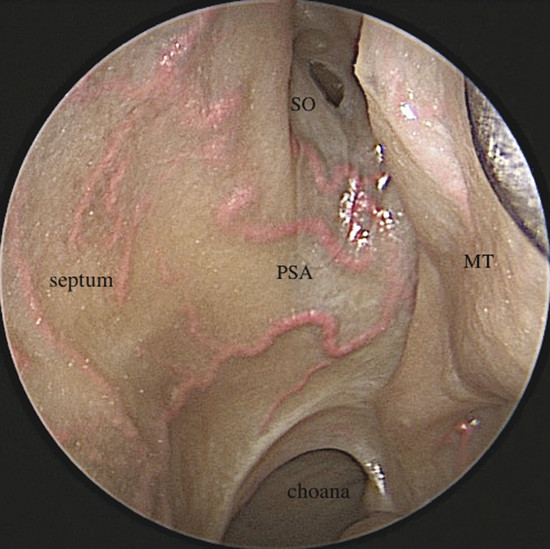

The PSA crosses the anterior wall of the sphenoid sinus in a subperiosteal plane, between the choana and sphenoidal ostium. In most cases the artery bifurcates into the superior and inferior branches (Fig. 3‑6). In this area it supplies the superior turbinate (superior turbinate artery), sphenoid sinus, and posterior ethmoid complex. The superior turbinate artery can arise from the superior division of the PSA or directly from the trunk of the PSA. 6 The PSA branches on the nasal septum irrigating the inferior two-thirds. The distal extreme of the inferior branch of the PSA, the nasopalatine artery, vascularizes the inferior septal area and ends in the incisive canal where it anastomoses with the greater palatine artery (GPA). 1 , 2 Furthermore, the PSA presents anastomosis in the septal area with the ethmoidal arteries and with branches from the SLA (Fig. 3‑7).